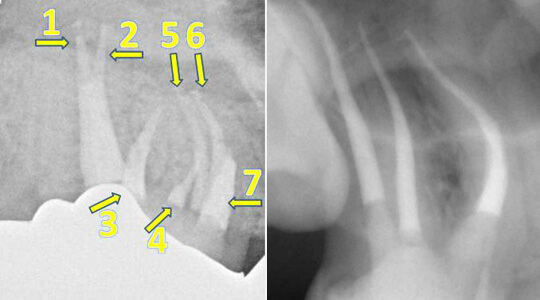

Ziel dieser Maßnahmen ist es, das ursprüngliche Kanalsystem möglichst in einen keimarmen und sauberen Zustand zu bringen. Dieses hört sich zunächst sehr einfach an, doch bergen z. B. kleine Seitenkanäle die Gefahr einer möglichen Reinfektion (siehe Pfeile in Bild links und rechts). Auch diese müssen sorgfältig gereinigt und möglichst perfekt aufgefüllt werden. Aus diesem Grund nehmen wir uns für Ihren Zahn die entsprechende Zeit, um die oben beschriebene chemomechanische Desinfektion durchzuführen.

Manchmal weisen die Zähne auch komplizierte anatomische Merkmale auf, die wir mit besonderer Sorgfalt behandeln müssen. Dazu gehören zum Beispiel eine überdurchschnittliche Anzahl an Wurzelkanälen (Bild links) oder starke Wurzelkrümmungen (Bild rechts): Oberer Backenzahn mit trotz starker Wurzelkrümmung erfolgreich gereinigten und aufgefülltem Wurzelkanalsystem.